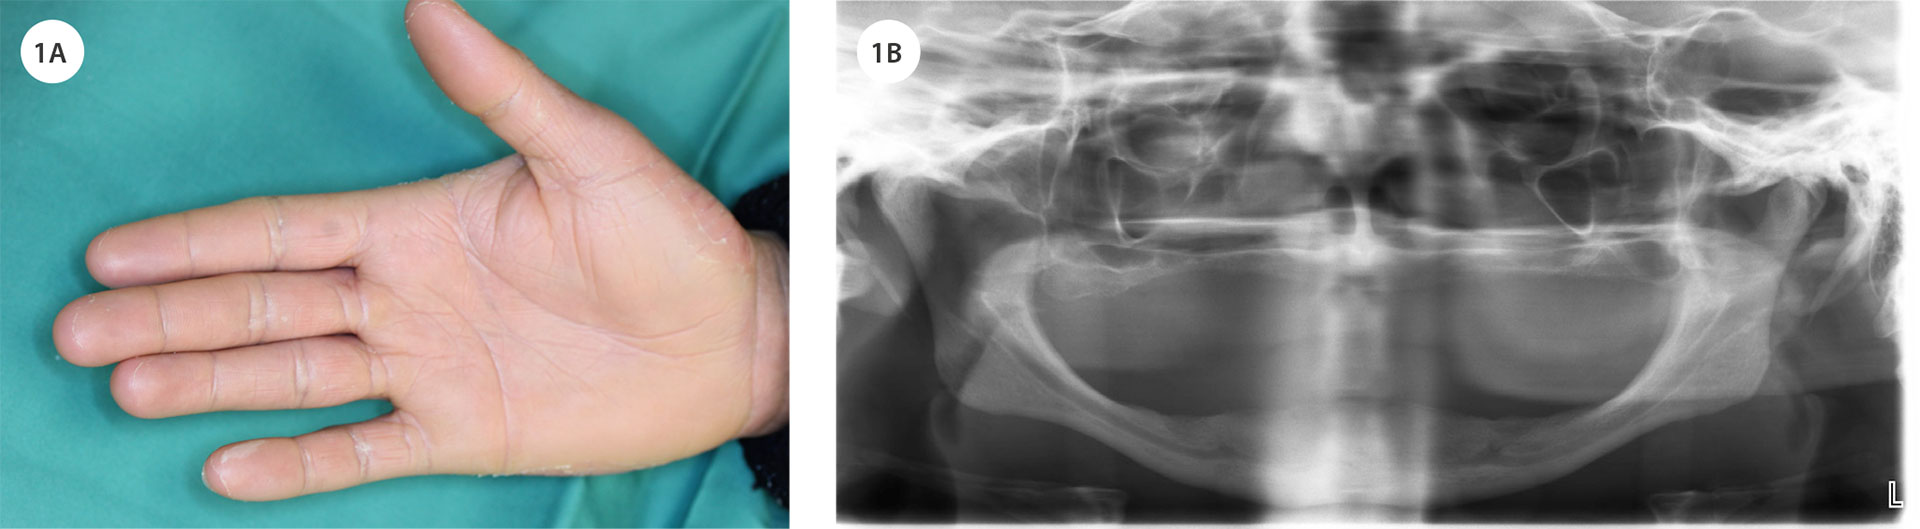

En 26 år gammel mann med flyktningbakgrunn, helt tannløs i både over- og underkjeven, ble henvist til Ålesund sykehus av sin tannlege for vurdering av implantatbehandling. Pasienten hadde tidligere fått diagnosen kronisk lichenifisert dermatitt med affeksjon av fot- og håndflatene (figur 1A), og behandles med Neotigason (Acitretin) kapsler, Daivobet (Betametason, Kalsipotriol) salve og Canoderm (Karbamid) krem. Ved klinisk undersøkelse ble det observert redusert leppestøtte i begge kjever grunnet tannløshet. Kjevekammene var sterkt atrofiske både i bredde og høyde, særlig i overkjeven (figur 2A). Munnslimhinnen fremsto frisk og fuktig. Håndflatene viste tørre, tykke og skjellende hudforandringer (figur 1A). Radiologiske undersøkelser med OPG (figur 1B) og Conebeam CT bekreftet uttalt atrofi av kjevekammene i begge kjever.

Figur 1. A: Pasienten hadde markante hudforandringer i hånd- og fotflatene, preget av uttalt tørrhet, fortykket hud og skjellende overflate, forenlig med palmoplantar keratodermi. B: Orthopantomogram viser uttalt kjeveatrofi i både over- og underkjeve, med betydelig reduksjon i benvolum spesielt i overkjeven.

Pasienten opplevde total tannløshet i over- og underkjeve som betydelig belastende, både funksjonelt og estetisk. Han uttrykte et klart ønske om en fast protetisk løsning, og ønsket ikke behandling med avtakbar protese. På grunn av alvorlig periodontitt og tidlig tanntap forelå det uttalt kjeveatrofi i begge kjever, noe som kompliserte behandlingsplanleggingen. Ved klinisk og radiologisk vurdering ble det imidlertid konkludert med at benvolumet i underkjeven var tilstrekkelig for innsetting av to implantater som støtte for en dekkprotese (figur 1B, 2A). Overkjeven viste derimot omfattende atrofi, og det ble vurdert som nødvendig med bentransplantasjon fra hoftekam før implantatbehandling kunne gjennomføres (figur 1A, 2A). Pasienten ble grundig informert om behandlingsalternativer, prosedyre og forventet forløp, og ga sitt informerte samtykke til videre behandling.